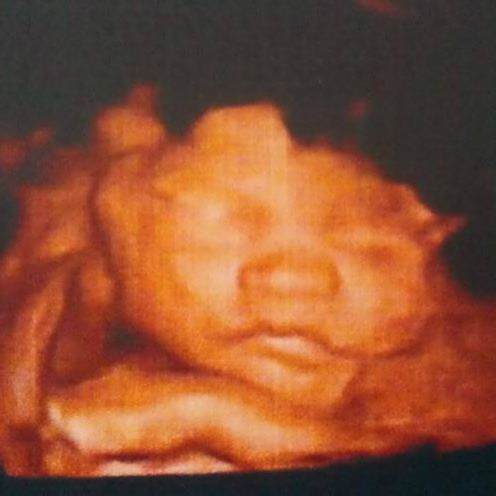

大西沿线网络太差,这图的原处是北六堡物流中心